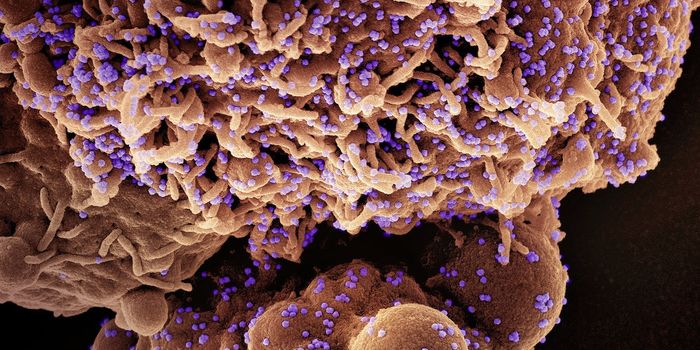

MAR 28, 2024CancerPublic domain via Wikipedia. Source: NIH Author: National Library of Medicine As we near the close of W ...